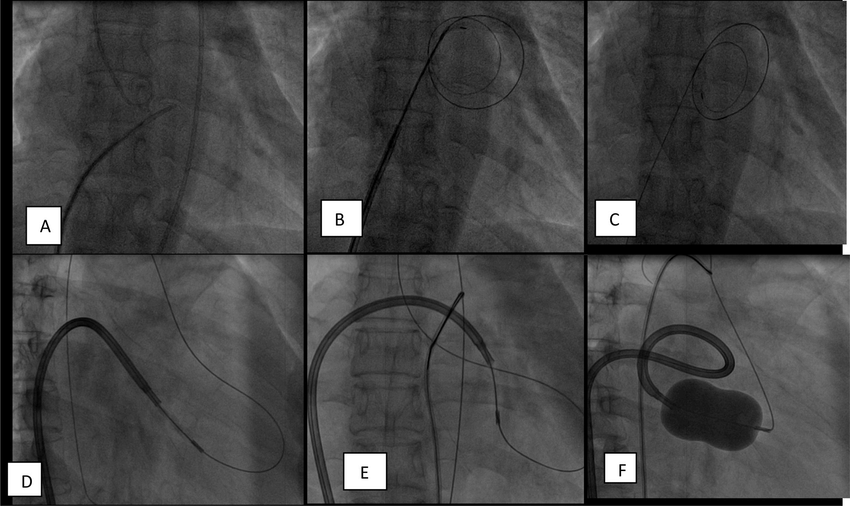

⚙️ نحوه انجام بالون دریچه میترال

والوپلاستی میترال در بخش آنژیوگرافی و بدون بیهوشی عمومی انجام می‌شود.

مراحل:

• ورود از طریق ورید کشاله ران

• هدایت بالون به قلب

• عبور از دریچه میترال تنگ

• باد شدن بالون و باز شدن چسبندگی‌ها

✅ افزایش بیش از 50٪ سطح دریچه معیار موفقیت عمل است.

A-Transseptal-puncture-B-transseptal-dilatation-C-0025-00-stainless-steel-floppy